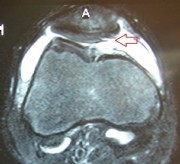

Severe cartilage damage to the patella in an MRI representation

With a tweezer the bone can be reached, the cartilage layer is severely damaged

After cleaning, removal of dead cartilage and replacement of the kneecap back surface with new cartilage